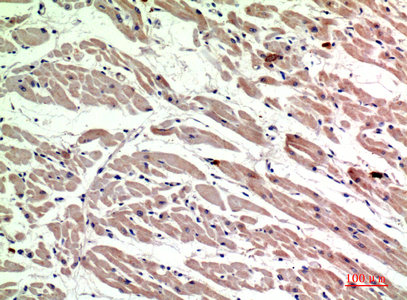

Immunohistochemical analysis of paraffin-embedded human-heart, antibody was diluted at 1:200